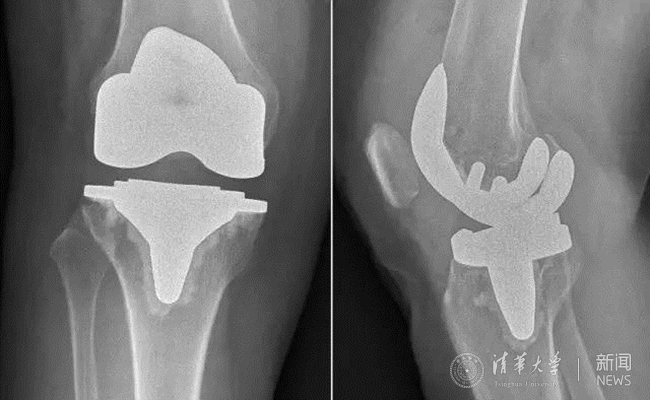

患者术后膝关节平片。

疗效改善的同时,新型假体对手术精准度的要求也提高了,为此,蔡谞教授和关节中心团队做了充足的准备,术前对手术参与人员进行了严格的操作训练。手术全程1个小时左右顺利结束,术后影像显示,新型假体安放位置精确,患者术后第2天即开始下床进行功能锻炼,术后7天顺利出院。